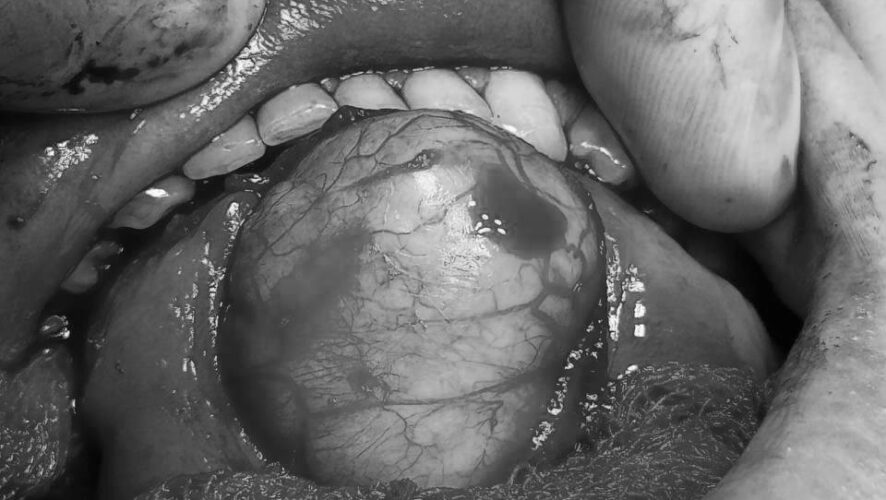

Образование во рту разрослось настолько, что мешало разговаривать.

Это образование выросло у парня буквально за полтора месяца. Молодой человек рассказал, что почувствовал во рту что-то растет. Пока он проходил обследования, образование во рту разрослось настолько, что мешало разговаривать.

Как выяснилась, это врожденная дермоидная киста, о которой раньше молодой человек не подозревал. Его прооперировал челюстно-лицевой хирург Райнур Мухаметзянов вместе с ассистентом, они аккуратно удалили кисту через разрез во рту. Через четыре дня пациента выписали домой.